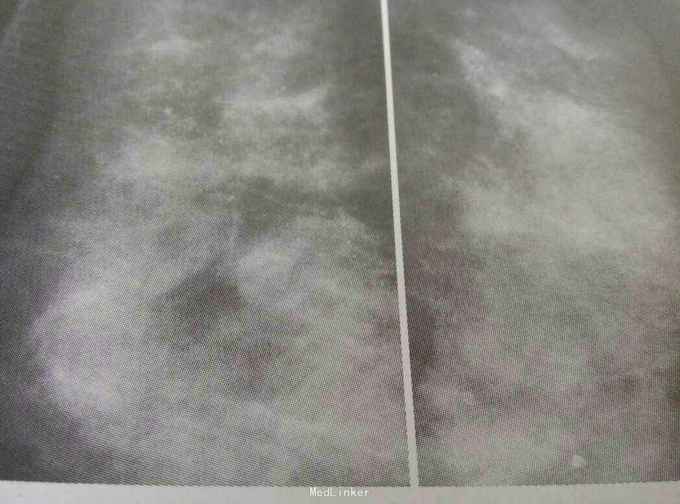

患者,女,50岁,乳腺体检时发现双乳多发钙化

查体:未及明显异常。 辅助检查:超声未发现明显异常,可见多个大小约0.3-0.5cm低回声区,乳腺增生明显。 钼靶:双乳上方多发散在分布的细小钙化,钙化大小密度不均,建议定期随访或切取活检。

诊断:乳腺良性钙化 治疗:局麻下行双乳钙化灶切取活检术,术后病理示:乳腺纤维囊性乳腺病伴导管内钙化。

随访:患者术后定期复查,未发现明显异常。 讨论:其实一看钼靶就比较倾向良性的钙化,但考虑患者年龄以及患者自身忧虑的心态,故考虑活检。这类病人一般为良性钙化,即纤维囊性乳腺病,但偶尔也能发现比较早期的乳腺癌,大多为原位癌,但我们不建议过度医疗。